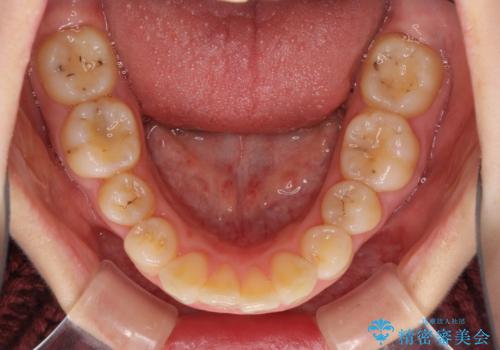

下顎は左右2番目の歯が2本欠損しており、上下前歯の前後的な位置は著しくずれている状態でした。

矯正治療後には、上顎欠損部をオールセラミックブリッジにて補綴治療を行うこととしました。